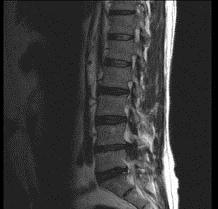

男,52岁,“坐骨神经痛”3个月余,请结合影像学检查,选出最可能的诊断 ( )A、椎间盘突出B、神经根鞘囊肿C、椎间盘炎D、硬...

相关内容:坐骨神经痛,月余,影像学,检查,选出,可能,诊断,椎间盘,神经,根鞘,囊肿